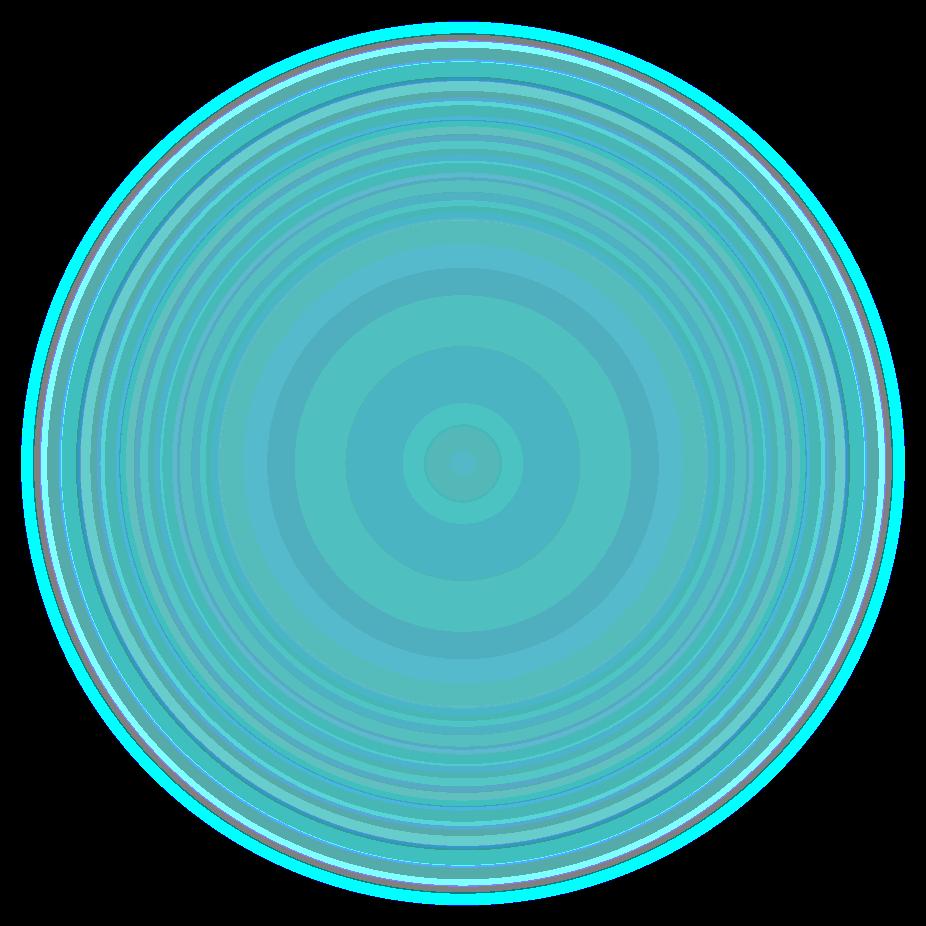

Diafragma “colgante” (“dangling sign”)

(“Dangling sign”)

TC. Mejor con multicorte. (reconstrucciones).

Asociación: Aire en pared.

Fracturas costal .Rotura esplénica. Neumoperitoneo.

Diafragma discontinúo Herniación de la grasa omental

Desser TS et al.The dangling diaphragm sign: sensitivity and comparison with existing CT signs of blunt traumatic diaphragmatic rupture. Emerg Radiol 2010